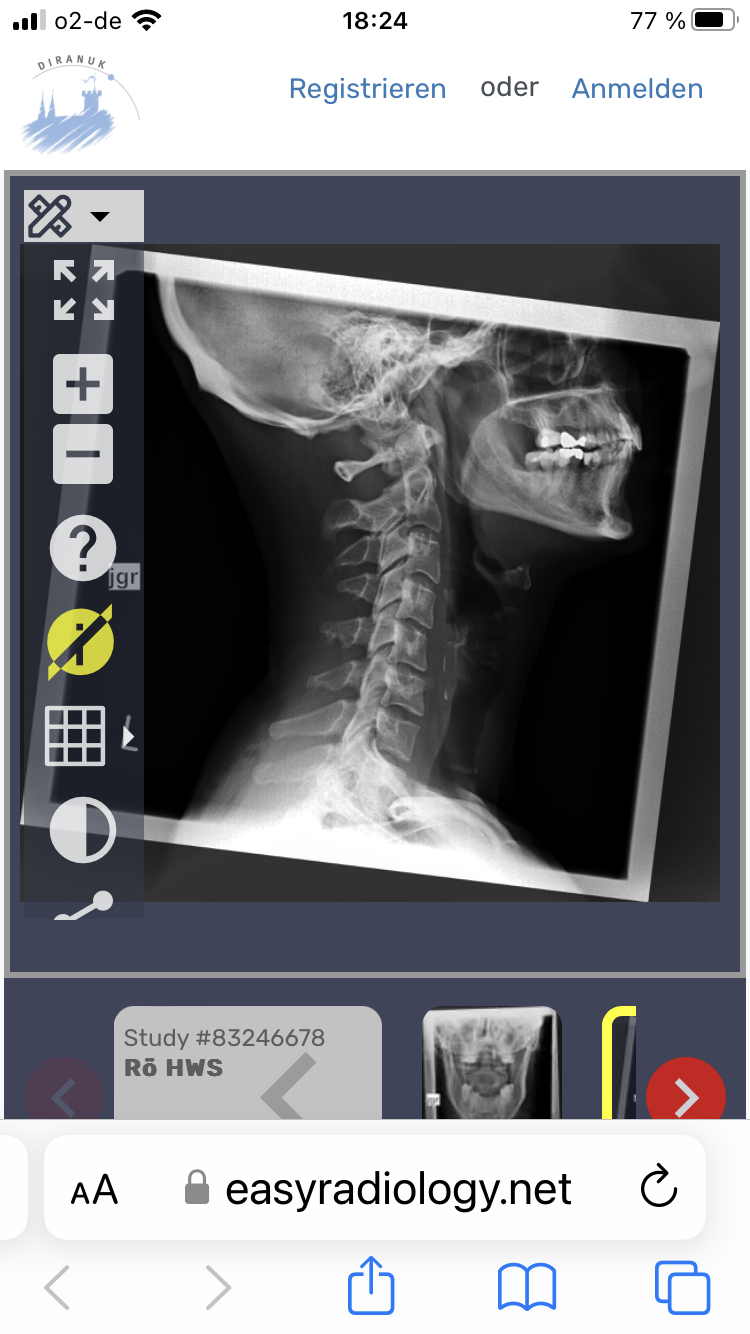

Tinnitus, Schwindel, Kopf- und Nackenschmerzentopic antwortete auf danieks daniek in: Patientenforum Hallo Oli, leider bin ich das Problem weiterhin nicht los geworden und nach wie vor (seid nun knapp 4 Monaten) krank geschrieben. Ich habe nun endlich einen guten Orthopäden gefunden, der mich zum Funktionsröntgen geschickt hat. Auf dem Bild war sichtbar, dass sich der Atlas verschoben und verdreht hat. Der Orthopäde möchte diesen nun beim nächsten Termin korrigieren- ich hoffe einfach das es was bringt und die Odyssee dann ein Ende hat. Zusätzlich bin ich bei einem CMD Spezialisten gewesen und habe eine spezielle Schiene bekommen- bisher merke ich hier aber noch keine Besserung. Konnte bei deiner Freundin schon etwas festgestellt werden? Was mir zumindest etwas geholfen hat ist Ergotherapie und Omega 3 Kapseln.

Hallo zusammen, aufgrund permanenter Nackenschmerzen und weiteren Symptomen wie Schwindel, Tinnitus und Gangunsicherheit wurde bei mir eine Atlasblockade vermutet. Ich habe eine Atlastherapie bei einer speziell dafür ausgebildeten Ergotherapeutin gemacht. Sie meinte der Atlas müsste nun korrekt sitzen. Leider haben sich meine Beschwerden jedoch nicht verbessert und ich ging nochmal zu einem anderen Orthopäden. Dieser vermutet weiterhin eine Atlasblockade und schickte mich zum Funktionsröntgen nach Gutmann/ Biedermann. Die Bilder habe ich einmal angehangen. Leider habe ich den Folgetermin beim Orthopäden erst Mitte Februar und bin nun schon bereits seit Oktober krank geschrieben. Kann man auf den Fotos ggf. eine Atlasblockade erkennen oder bin ich da auf dem völlig falschen Weg? Ich würde gerne endlich wieder arbeiten und zumindest die Schmerzen ein wenig reduzieren können( diverse Schmerzmittel und Muskelentspannungstabletten helfen nicht). Wie wäre anhand der Bilder Eure Einschätzung (mir ist bewusst, das ersetzt natürlich keine ärztliche Untersuchung/ Meinung). schon jetzt vielen Dank! P.S. ein MRT wurde ebenfalls von HWS und BWS gemacht hier wurden zwar Vorwölbungen und Facettengelenksarthrose festgelegt allerdings keine Einengung oder Kompressionen von Nerven etc. Aber diese Schmerzen und der Tinnitus machen mich einfach nur irre!